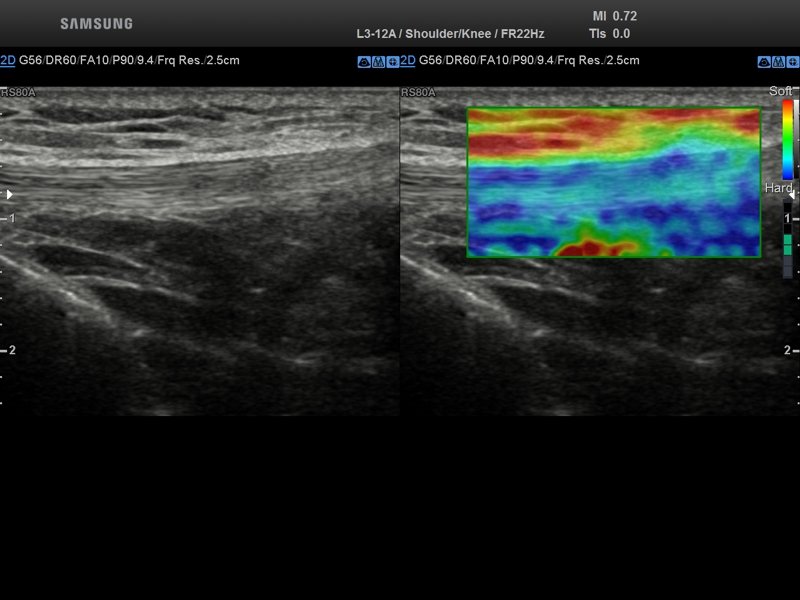

Patellar ligament, Elastoscan (echogramm №849)

[RU] Ultrasound image №849: Own patellar ligament in elastography mode.

Echogramm was received by ultrasound scanner RS80 (out of production).